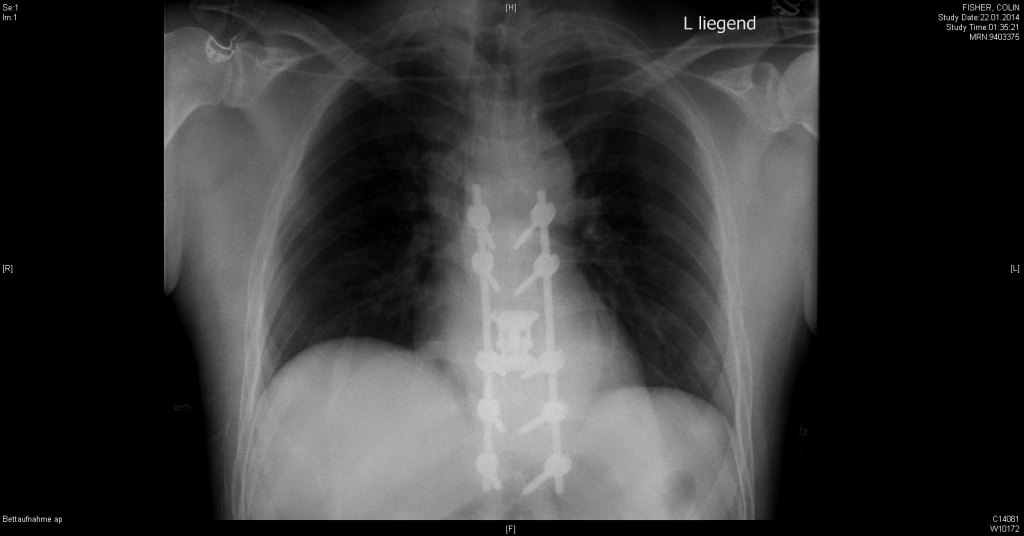

On the 21st January 2014 I had a skiing accident and broke my back. I destroyed my T9 vertebra. I was taken to the Kantonsspital in Chur for emergency surgery. Dr. Broger and his team spent 6 hours fitting a titanium cage to replace my vertebra and two poles to stabilise my spine. On the 22nd January Dr. Broger told me how incredibly lucky I was that not a single piece of my broken vertebra cut my spinal column. I was so very lucky not to need a wheelchair for the rest of my life.

This is what I looked like on the outside and the inside.

It changed my life. I decided to retire. As part of my recovery I had to find a sport. Contact sports and anything to do with running were not possible. I decided to try cycling. It all started at the Circuito Ciclistico Zengarini in Fano, Marche.